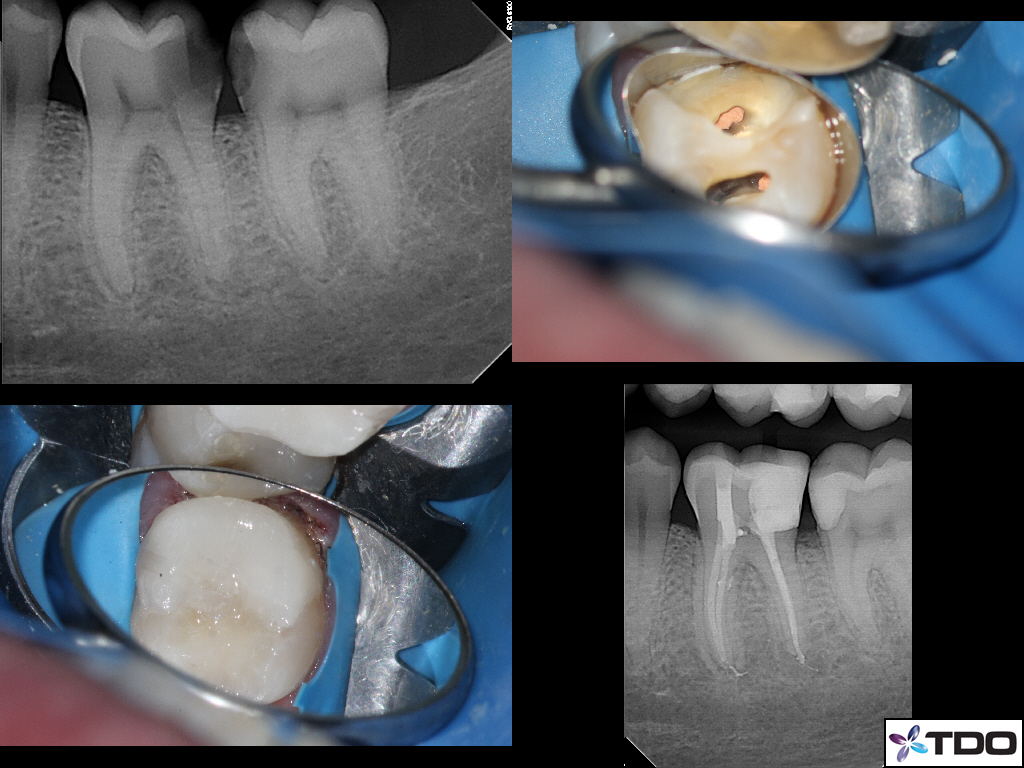

This 35 year-old male presented as an emergency with acute pain in the lower left quadrant. Obvious deep caries present in both #19 and #18. Tooth #19 was acutely painful to the touch. His general dentist told him that both teeth were non-restorable and needed to be extracted. He did not want to lose both of his teeth and asked what else he could do. They referred him to us. Completed root canal treatment with a “truss” access in two sessions and the tooth was asymptomatic prior to obturation. Tooth #18 did not expose the pulp so we just restored the cavity prep with a bonded resin. The patient is completely asymptomatic today. He does not wish to return to his general dentist.

At 35 years old, we should really be talking about saving these teeth in my opinion. Do we have 60 year implant outcomes yet? What if these teeth only make it until the patient is 60 years old? I feel much more comfortable with the patient proceeding with implant supported crowns at 60 than I do at 35. Just my opinion.

I simply cannot believe that not blowing this wide open, but instead preserving the truss between the B and L cusps as you have done here, does make the prognosis for this tooth 1000% better. Once restorative dentists start seeing how powerful this approach is to saving teeth, endodontists (except the most dogmatic) will come to understand that this approach shows endodontics in the BEST light —-as preservers of the dentition instead of as a “pre-implant procedure”.